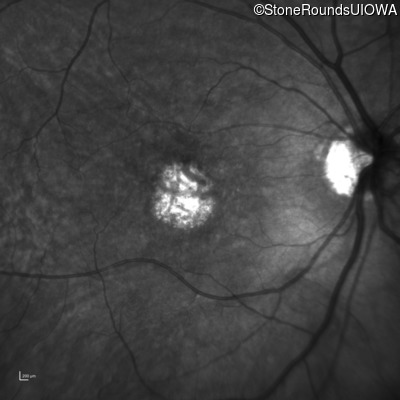

This 59 year old woman first noticed a reduction in her visual acuity and photophobia in her late teens.

| AD Cone and Cone Rod Dystrophy | GUCA1A | Glu155Gly GAG>GGG | AD |